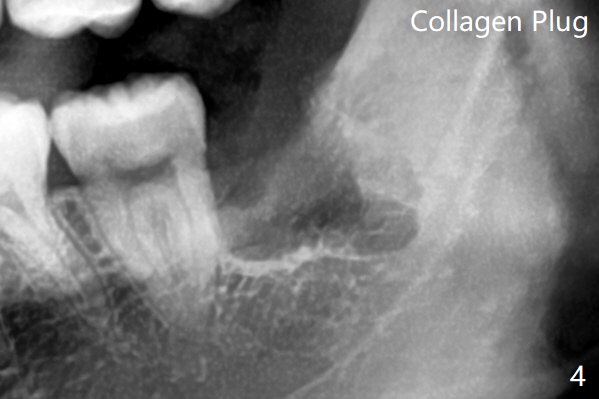

拔除后放置胶原塞(图四)。术后没有神经损伤症状。